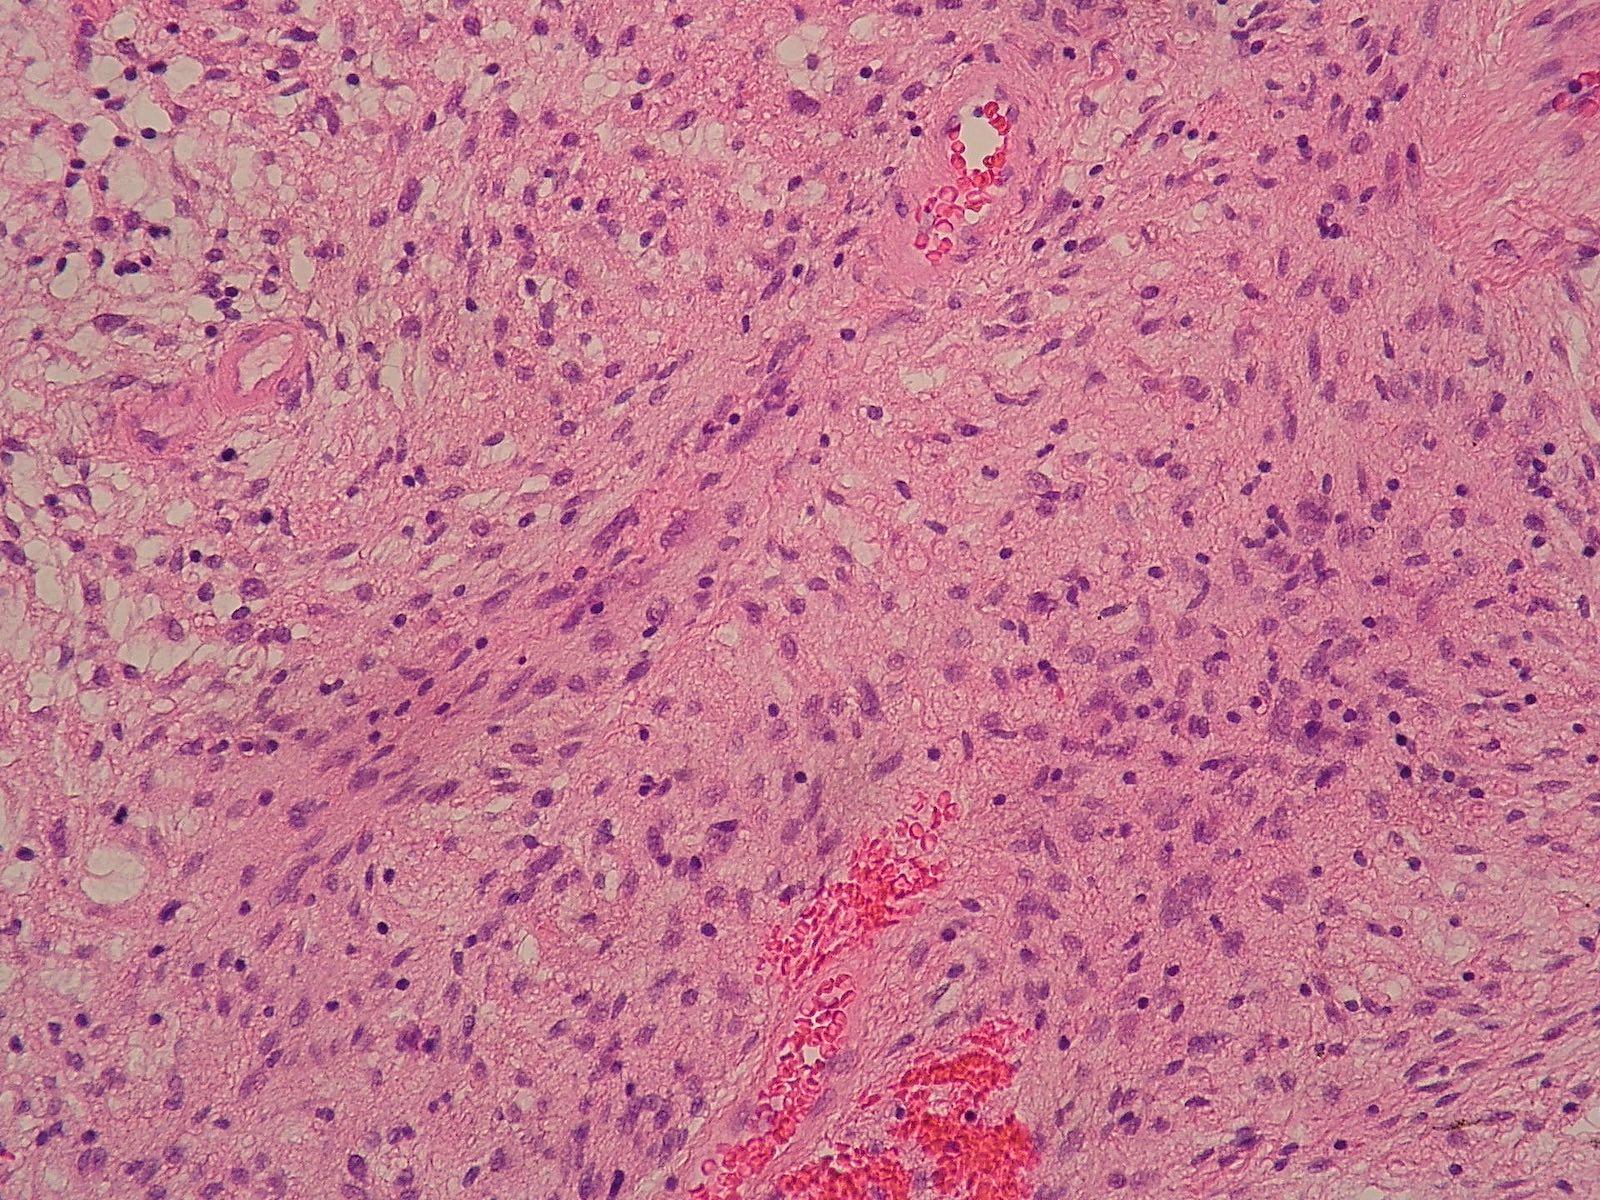

Microscopic (histologic) description

- Low to moderately cellular, bland fusiform or spindled cells with focal to diffuse whirling in heavily collagenized stroma with abrupt transition to myxoid areas

- 45% have epithelioid areas

- 40% contain poorly formed but large collagen rosettes

- Often infiltrates adjacent skeletal muscle

- Occasionally has areas of increased cellularity, atypia, necrosis or mitotic activity characteristic of intermediate to high grade sarcoma

- Recurrences may show increased cellularity and mitotic activity

Microscopic (histologic) images